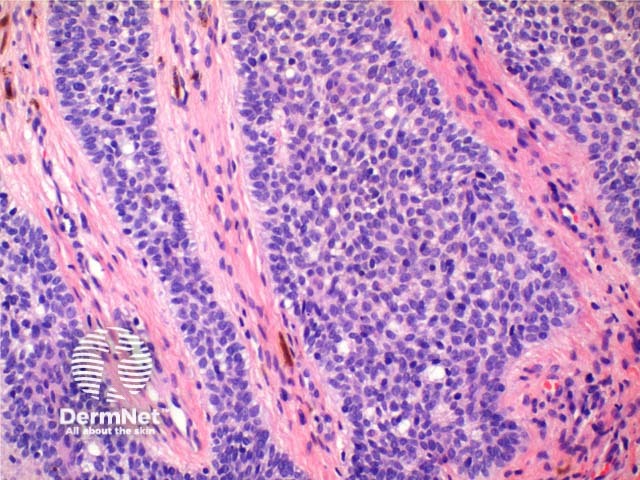

Scanning power view of the histology of syringofibroadenoma reveals an epidermal proliferative process (Figure 1). Vertically oriented anastamosing strands of basaloid epithelium are seen arising from multiple points along the epidermis (Figure 2). The basaloid cells are smaller than adjacent keratinocytes and show mild variation in size (Figure 4). Ductal differentiation is seen (Figures 3 and 4). The tumour has notable intervening fibrovascular stroma, and may have a mild superficial lymphocytic infiltrate (Figure 4).

Figure 4